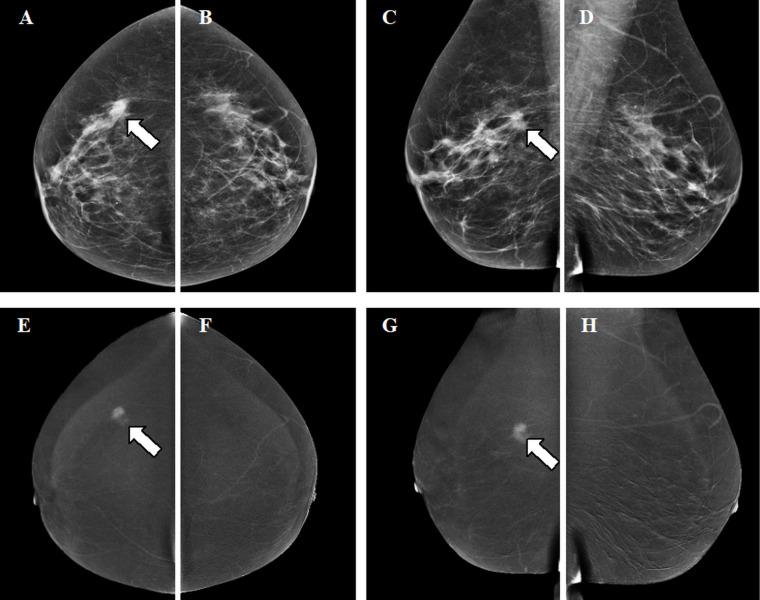

对比增强乳腺摄影:放射科医生需要了解的内容。

Contrast-enhanced mammography: what the radiologist needs to know.

Contrast-enhanced mammography (CEM) is a combination of standard mammography and iodinated contrast material administration. During the last decade, CEM has found its place in breast imaging protocols: after i.v. administration of iodinated contrast material, low-energy and high-energy images are retrieved in one acquisition using a dual-energy technique, and a recombined image is constructed enabling visualisation of areas of contrast uptake. The increased incorporation of CEM into everyday clinical practice is reflected in the installation of dedicated equipment worldwide, the (commercial) availability of systems from different vendors, the number of CEM examinations performed, and the number of scientific articles published on the subject. It follows that ever more radiologists will be confronted with this technique, and thus be required to keep up to date with the latest developments in the field. Most importantly, radiologists must have sufficient knowledge on how to interpret CEM images and be acquainted with common artefacts and pitfalls. This comprehensive review provides a practical overview of CEM technique, including CEM-guided biopsy; reading, interpretation and structured reporting of CEM images, including the accompanying learning curve, CEM artefacts and interpretation pitfalls; indications for CEM; disadvantages of CEM; and future developments.

摘要

对比增强乳腺摄影(CEM)是标准乳腺摄影与碘化造影剂注射的结合。在过去十年中,CEM在乳腺成像方案中占据了一席之地:静脉注射碘化造影剂后,使用双能技术在一次采集中获取低能量和高能量图像,并构建重组图像以实现对比剂摄取区域的可视化。CEM在日常临床实践中的应用增加体现在全球范围内专用设备的安装、不同供应商系统的(商业)可用性、CEM检查的执行数量以及关于该主题发表的科学文章数量上。因此,越来越多的放射科医生将面临这项技术,从而需要跟上该领域的最新发展。最重要的是,放射科医生必须具备足够的知识来解读CEM图像,并熟悉常见的伪影和陷阱。这篇综述全面介绍了CEM技术,包括CEM引导下的活检;CEM图像的阅读、解读和结构化报告,包括伴随的学习曲线、CEM伪影和解读陷阱;CEM的适应证;CEM的缺点;以及未来的发展。